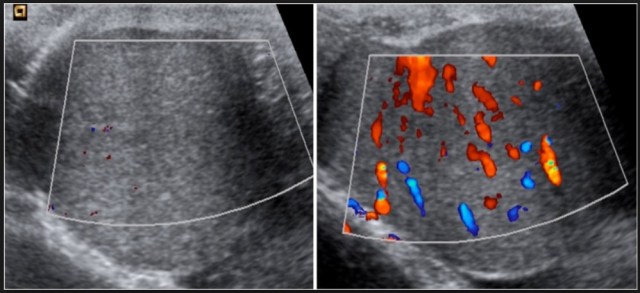

La Ecografía convencional es una prueba poco específica y con grandes limitaciones para el diagnóstico de la torsión testicular pudiendo encontrarse tanto un patrón hipoecogénico como hiperecogénico en función al grado evolutivo de la torsión.

La Ecografía aunada al Doppler Color es el estudio de elección para la valoración de la vascularización del cordón testicular y del testículo. Se asume que esta prueba tiene una Especifícidad del 100 % y una Sensibilidad del 80 %; aunque existe evidencia clínica que sugiere que la sensibilidad de la Ecografía Doppler podría ser más baja de lo esperado, en torno al 60 % dependiendo en gran medica del examinador. (

Izquierda; teste izquierdo con prácticamente ausencia de flujo sanguíneo. Derecha: teste derecho con flujo dopler normal.